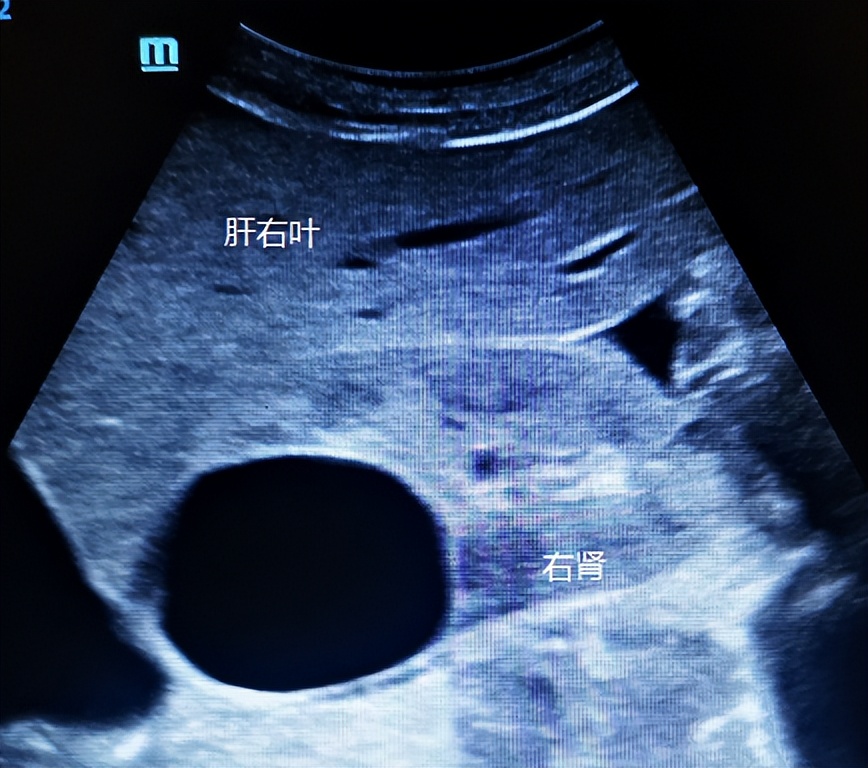

如下图,看似肝囊肿。

换个切面扫查,实则肾囊肿。